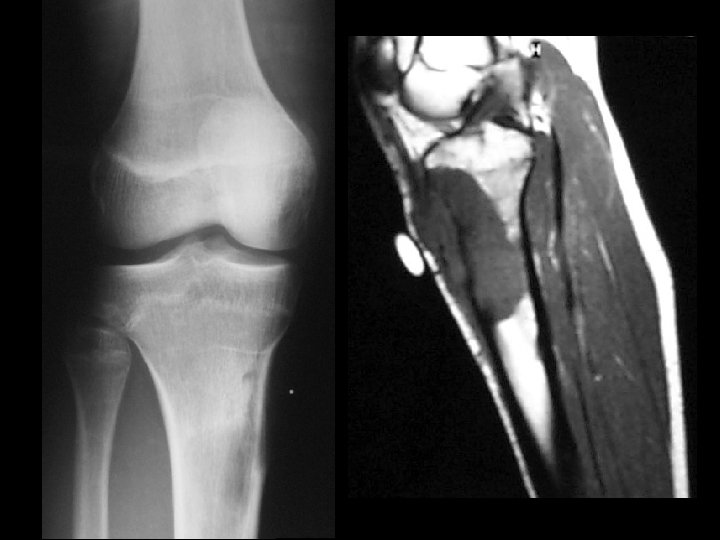

Giant cell tumor • Findings: – End of bone lucent and expansile lesion with a narrow zone of transition – No periosteal reaction or soft tissue mass • ddx: – ABC – metastasis – chondroblastoma

Giant cell tumor • Findings: – End of bone, eccentric, lucent lesion with narrow zone of transition but no sclerotic margin • ddx: – Fibrous dysplasia – ABC – Chondroblastoma